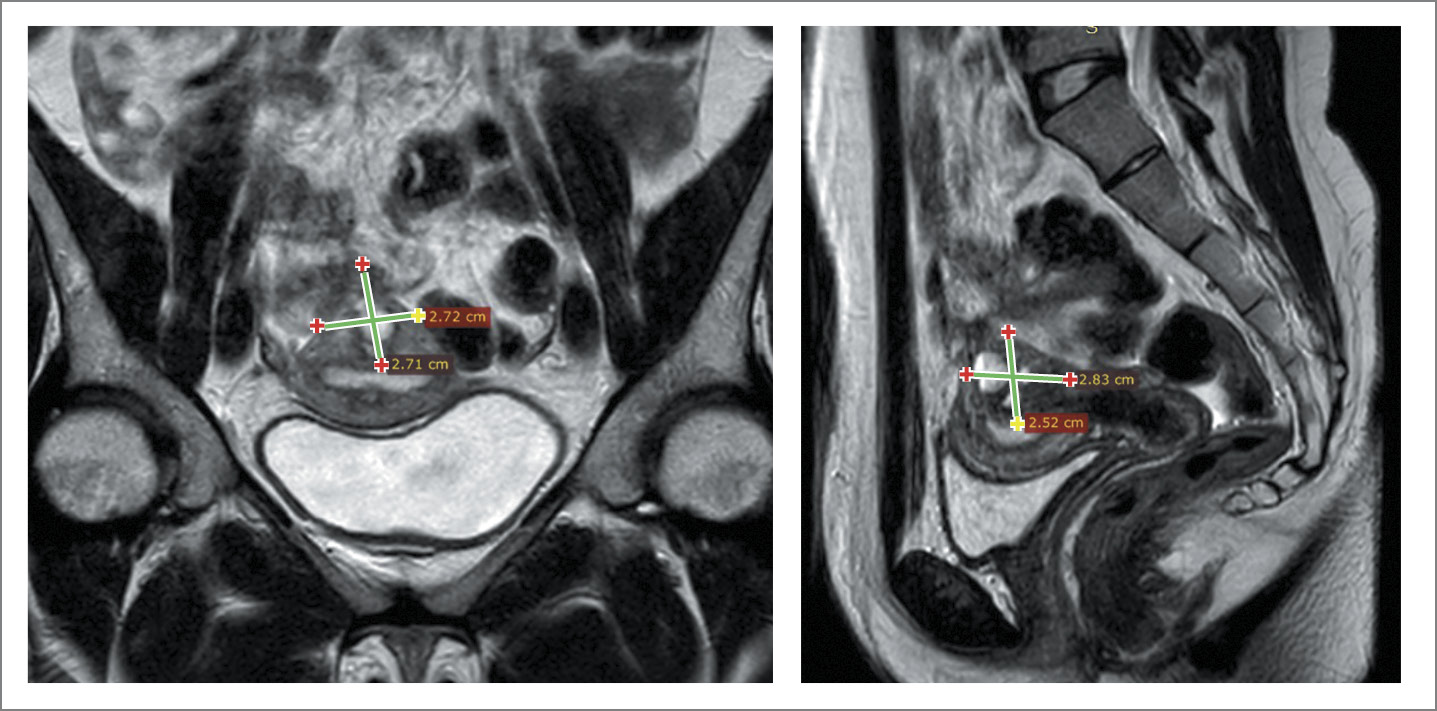

Рис. 1. МРТ-картина кистозного аденомиотического поражения задней стенки матки (многокамерная аденомиома матки). Визуализируется мультикистозное патологическое образование в миометрии размером 25×28×27 мм, отмечено слабое накопление контраста.

Fig. 1. MRI picture of cystic adenomyotic lesion of the posterior wall of the uterus (multi-chambered adenomyoma of the uterus). A multicystic abnormal mass was visualized in the myometrium, of 25×28×27 mm, with a low RPA uptake.